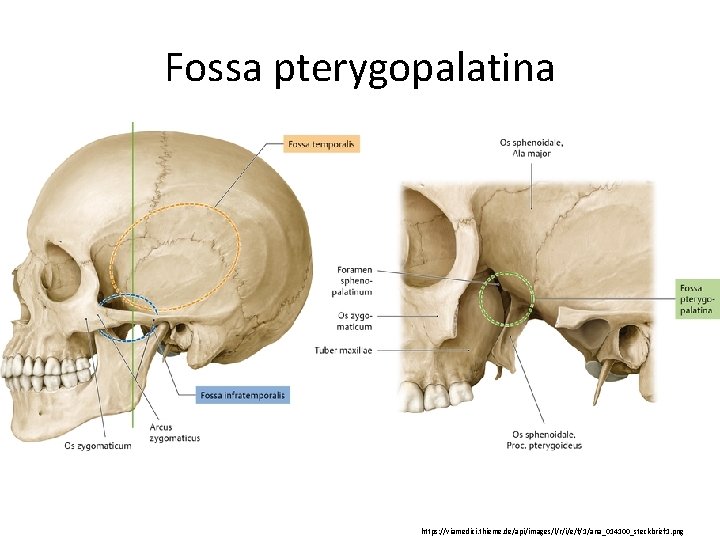

Анатомия и особенности фиссуры петротимпаника